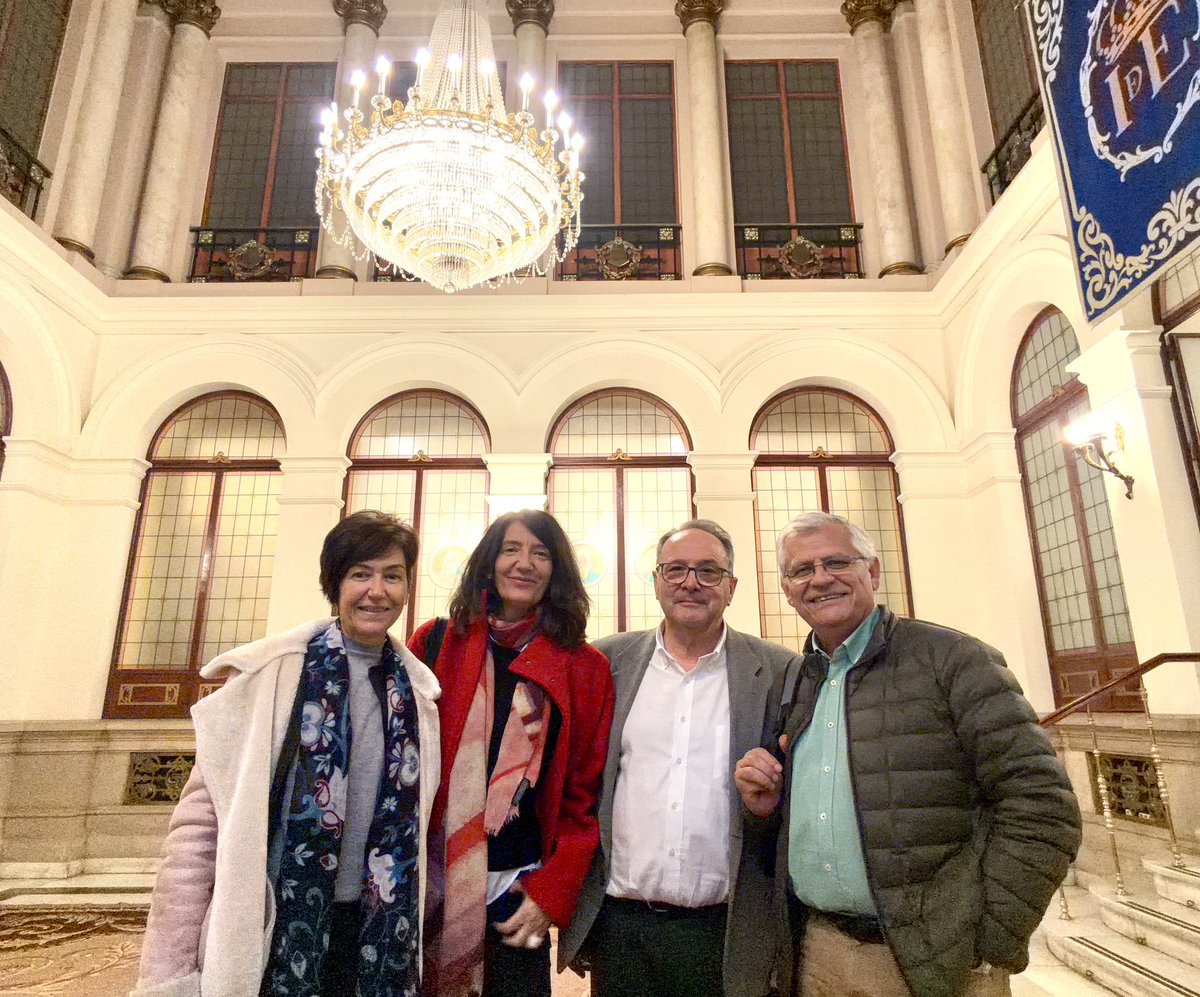

¡Ha sido un placer tenerte una vez más con nosotros, querido Guillermo! Pronto nos encontramos de nuevo al otro lado del océano Medicina UAM Química UCHILE 🇪🇸🇨🇱 🔬🧬 Isabel Sánchez Pérez Carlos Sánchez Ferrer

Deseando volver a encontrarnos con estudiantes, colegas y amigos de Química UCHILE Universidad de Chile. ¡Nos vemos enseguida para este curso sobre avances en mecanismos de acción de fármacos! 💊🧬🔬 #investigación #colaboración #internacinalización Carlos Sánchez Ferrer Isabel Sánchez Pérez

Las primeras jornadas de investigación y docencia en farmacología e inmunología fueron todo un éxito! Muchas gracias a todos los que participaron, en especial a nuestros expositores 👏👏👏👏 ICBM Concha Peiró Facultad de Medicina